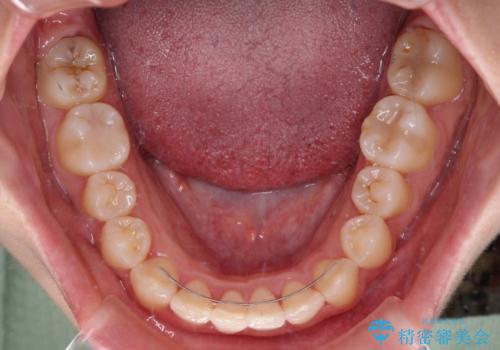

前歯部のデコボコがなくなったため、歯磨きしやすくなり、非常に清潔な状態になりました。

奥歯の咬み合わせを見ると、上顎臼歯が下顎に対して前方にあり、叢生改善により口元が突出する顔貌ではなかったため、上顎左右第一小臼歯2本を抜歯し、ワイヤー装置にて矯正治療を行うこととしました。